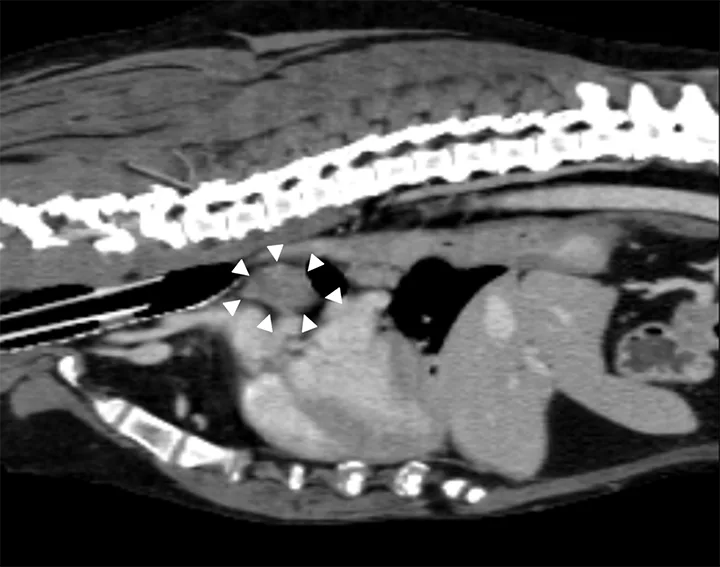

Dorsal CT image of a dog with arrows pointing to a large mass in the lungs.

FIGURE 1

Dorsal reformatting of a contrast-enhanced CT scan in the soft tissue of a patient with a primary lung tumor. A large (>6 cm in diameter) primary lung carcinoma (arrows) causing lateral deviation of the mainstem bronchi can be seen.